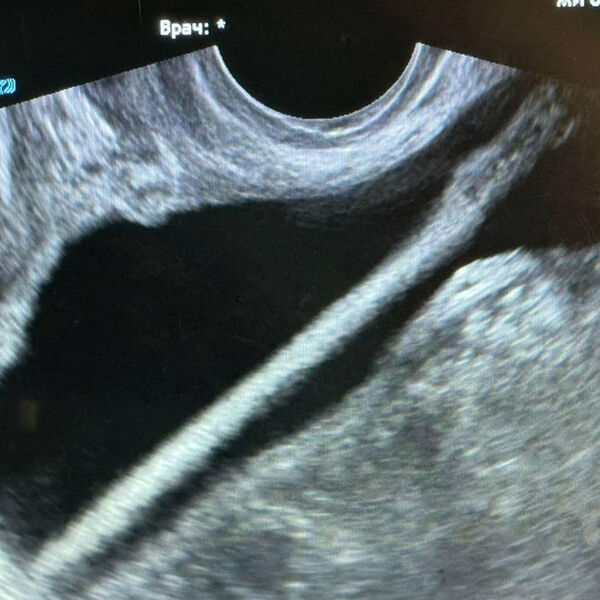

Инцидент произошел в Красногорской больнице. Пациентка обратилась в приемное отделение и рассказала, что ввела себе в мочевой пузырь через мочеиспускательный канал косметический карандаш. После обследования женщину госпитализировали в урологическое отделение.

С помощью эндоскопа хирурги извлекли инородное тело. Оперативное вмешательство прошло без осложнений, пациентку уже выписали домой. Однако медики предупредили, что подобные эксперименты могут привести к травмам, воспалениям и тяжелыми инфекциям.